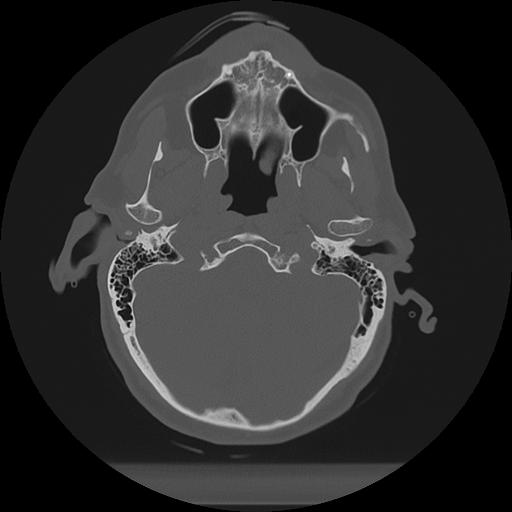

11 HUESO,,Axial,2.0,HUESO,,